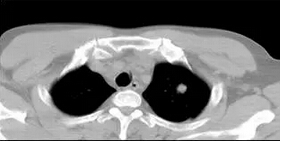

CT檢查發(fā)現(xiàn)左上肺有一個(gè)不足1cm的病灶,通過(guò)支氣管鏡無(wú)法取得活檢結(jié)果,這個(gè)病灶比較深,又非常小,要取得活檢標(biāo)本同時(shí)盡量避免并發(fā)癥,非常考驗(yàn)水平。

達(dá)到這一目的,要求快、準(zhǔn)、穩(wěn),我們幸運(yùn)的做到了,僅一次穿刺就把活檢針?lè)胖玫侥[瘤邊緣,取得了滿意的組織標(biāo)本。再看安全性,穿刺活檢完成后掃描沒(méi)有一點(diǎn)氣胸,是一個(gè)完美的小病灶穿刺活檢。